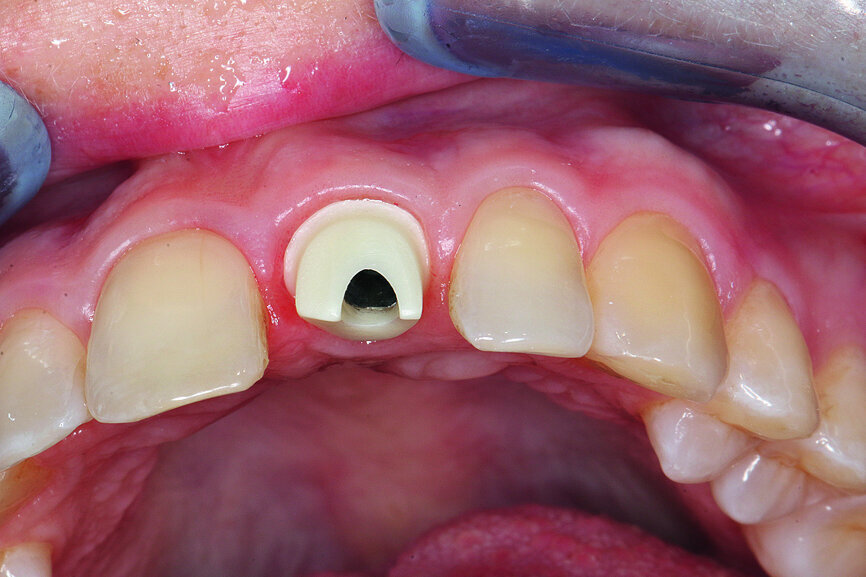

Fig. 12: The screw-retained crown as a finished polished temporary.

Fig. 13: Sealing the screw channel with composite.

Fig. 16: Inserting the abutment with the transfer key.

Fig. 17: Complete preservation of the vestibular contour.

The temporary was then removed, and the abutment was inserted using a transfer key. The vestibular contour was completely preserved (Figs. 16 & 17). After sealing the screw channel with a PTFE strip, an all-ceramic, custom-veneered crown was inserted for a perfect aesthetic outcome of the anterior tooth (Fig. 18).